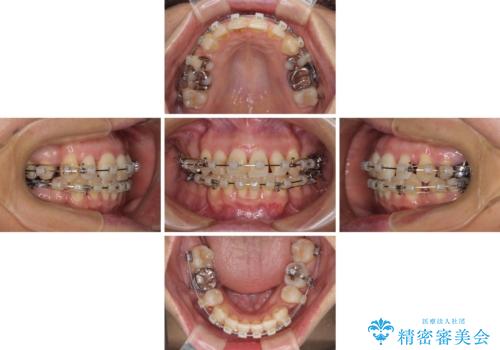

八重歯で口元が膨れている ワイヤー装置での抜歯矯正

- クリアブラケット

- 2年2ヶ月

八重歯・デコボコの解消とともに、前方に張り出した上顎前歯を引っ込めることを目的とし、上下左右の第一小臼歯4歯を抜歯をしてワイヤー矯正により治療することとしました。

半年もしないうちに八重歯は解消し、治療も当初予定通り2年強で終えることができました。